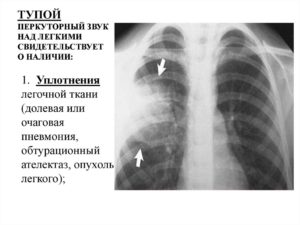

При этих состояниях температуры может и не быть или она возникает периодически и повышается до 37 или чуть выше градусов. В основе образованиях патологических шумов два процесса:

- Изменение нормального состояния стенок бронхов, что приводит к сужению их просвета.

- Нахождение в сосудах дыхательной системы слизистых или гнойных масс с разной степенью их вязкости. Этот секрет под воздействием воздуха начинает колебаться, и возникают разные звуки во всех отделах легких и в бронхах.

При прослушивании дыхательной системы врач обращает внимание на разные характеристики звуков, то есть на их звучание. Когда они образуются – на вдохе или выдохе. Диагностическое значение имеет и как проявляются влажные хрипы в легких. Они могут быть крунопузырчатыми, средними и мелкими.